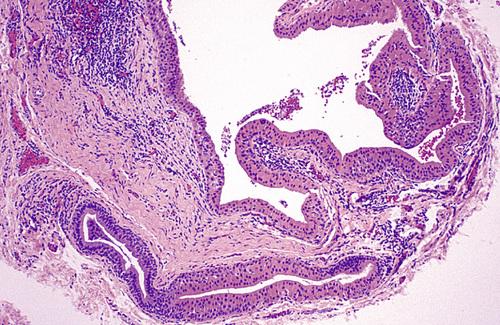

Radiopaque mass located at the left angle of the mandible. They may be discovered anywhere along the length of the duct or within the gland itself.

sialolith

- Periapical film showing discrete radiopacity superimposed on the body of the mandible. Care must be taken not to confuse this with intrabony pathosis.

- Occlusal radiograph of same patient demonstrating radiopaque mass in Wharton duct.

sialolith

- A mass of a minor gland presenting as a hard nodule in the upper lip.

- A soft tissue radiograph revealed a laminated calcified mass.

sialolith